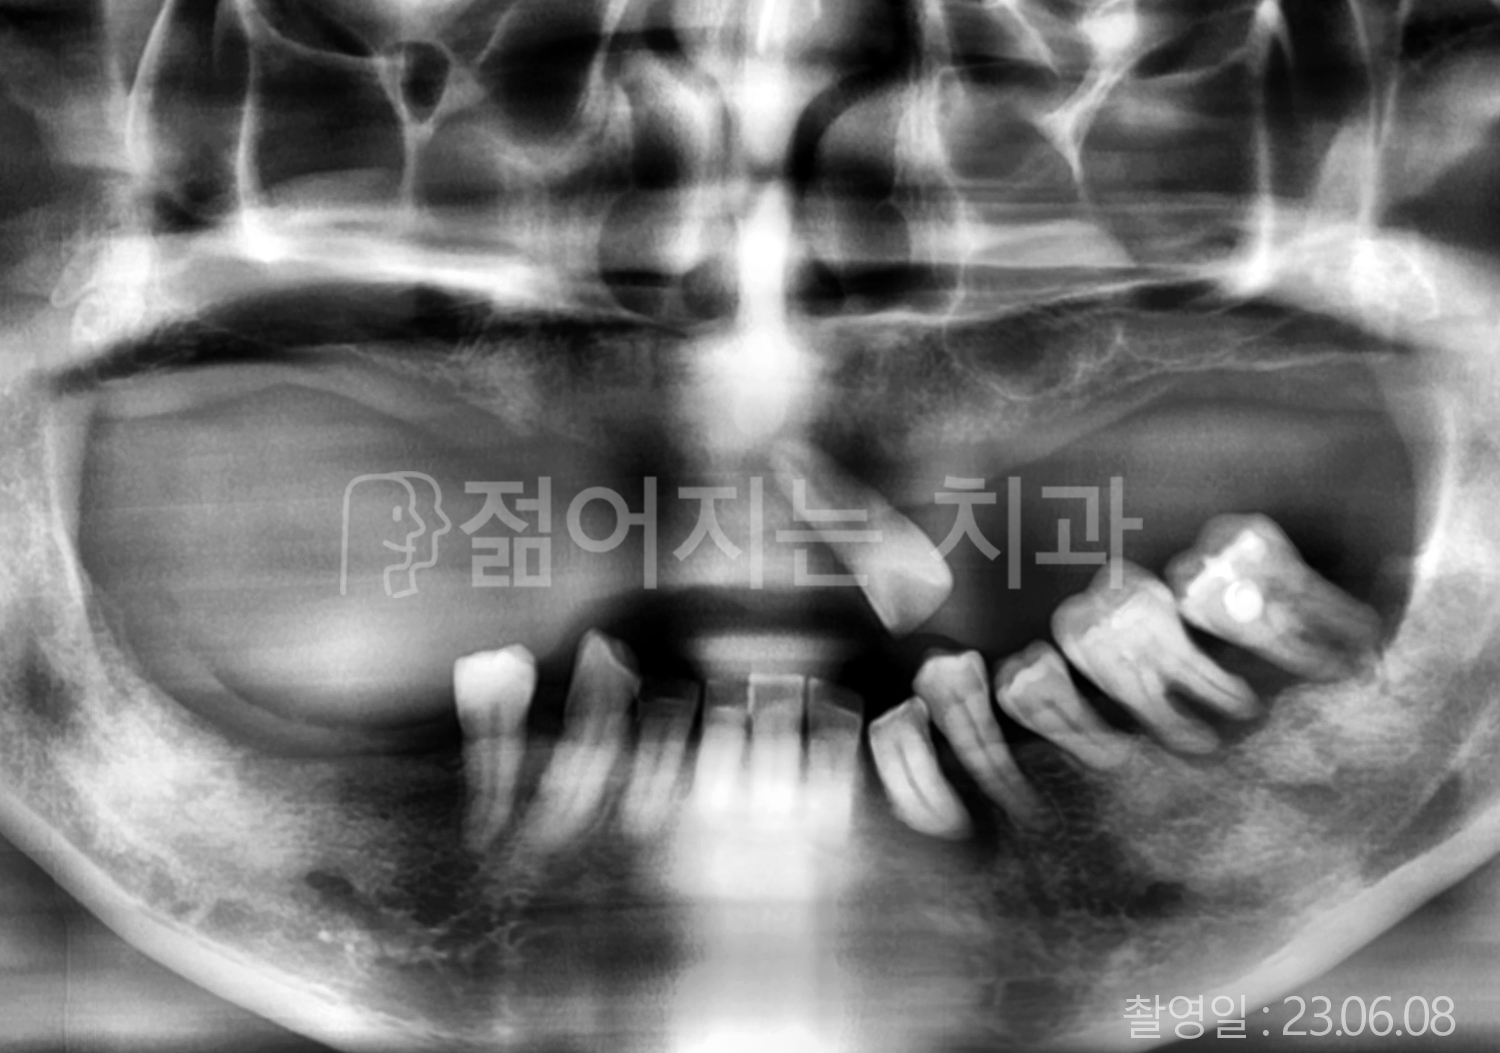

• 60대 전체치아 10개 이상 임플란트